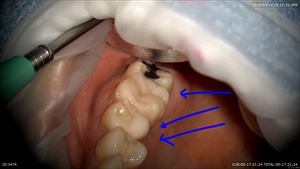

ここです。手前の3本は当院でマイクロスコープを使用し施術。予後は良好です。

さて本日の歯の金属を外し